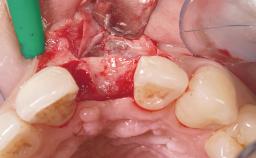

Placement Protocol Immediate implant placement

Socket Morphology Single-root socket

Socket Integrity Damage to one or more bone walls

Bone Volume Damage to one or more socket walls